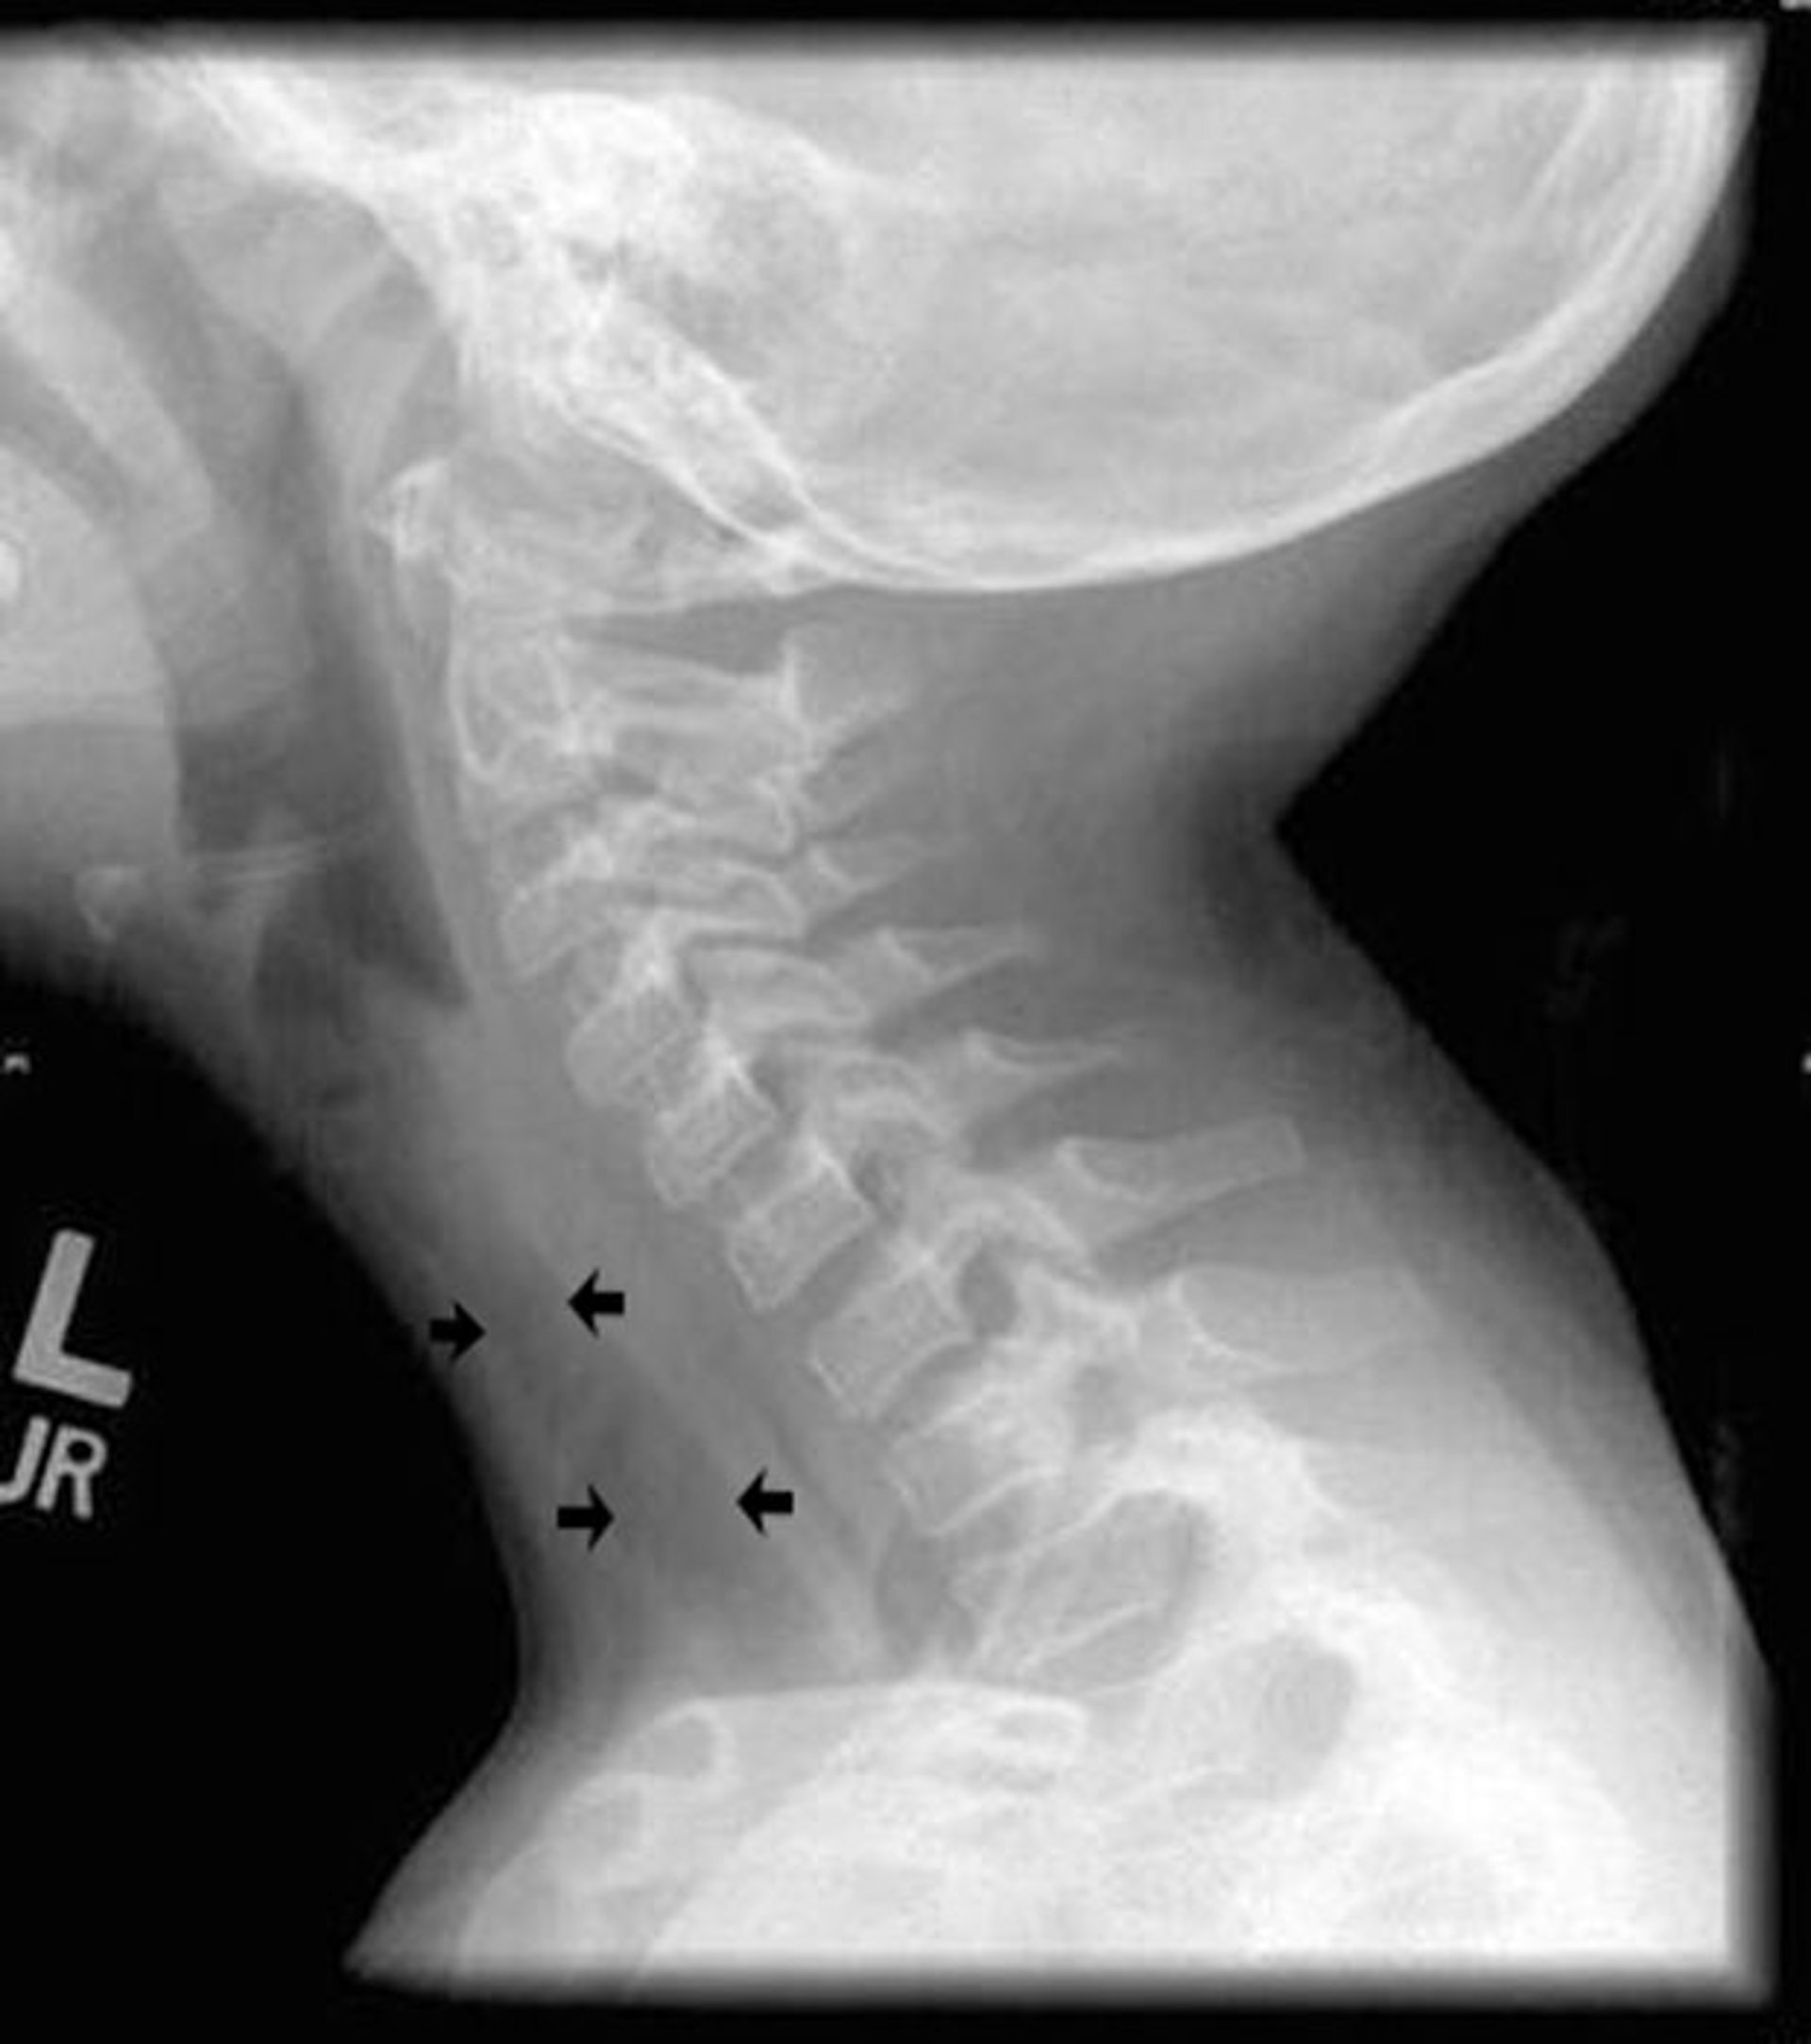

This lateral radiograph of the neck shows diffuse irregularity of the trachea (arrows) characteristic of bacterial tracheitis.

The esophagus is the tubular structure posterior to the trachea.